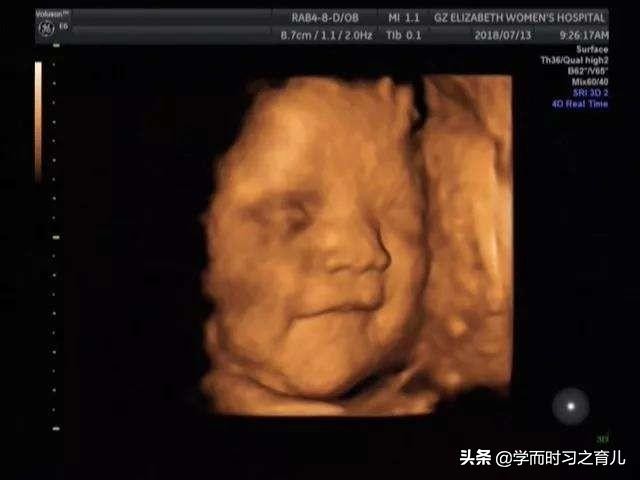

2、胎儿总是挡住脸

其实四维彩超对胎儿面部的检查内容还是比较多的,比如嘴巴、鼻子等等,但如果胎儿总是用手挡住脸,那医生就无法看清其局部发育情况,从而导致产检不顺利。

此外,针对这种现象,准妈妈是最无奈的,因为宝宝挡住脸,不像宝宝动得厉害,准妈妈还可以调整一下,一般宝宝挡住脸,孕妈咪不管做什么,宝宝都不会那么挺好的配合,当然了,有些宝宝比较听话,妈妈一说,宝宝就放下手了。